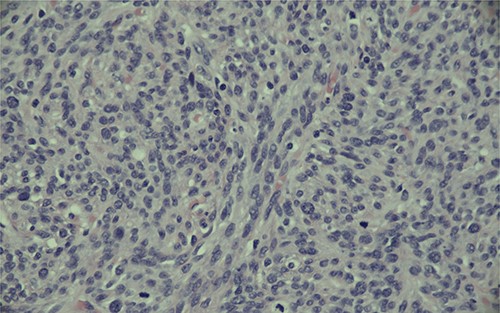

Magnification (200x) of histologic section of prostate, showing STUMP with severe cytologic atypia and no increase in mitotic activity.